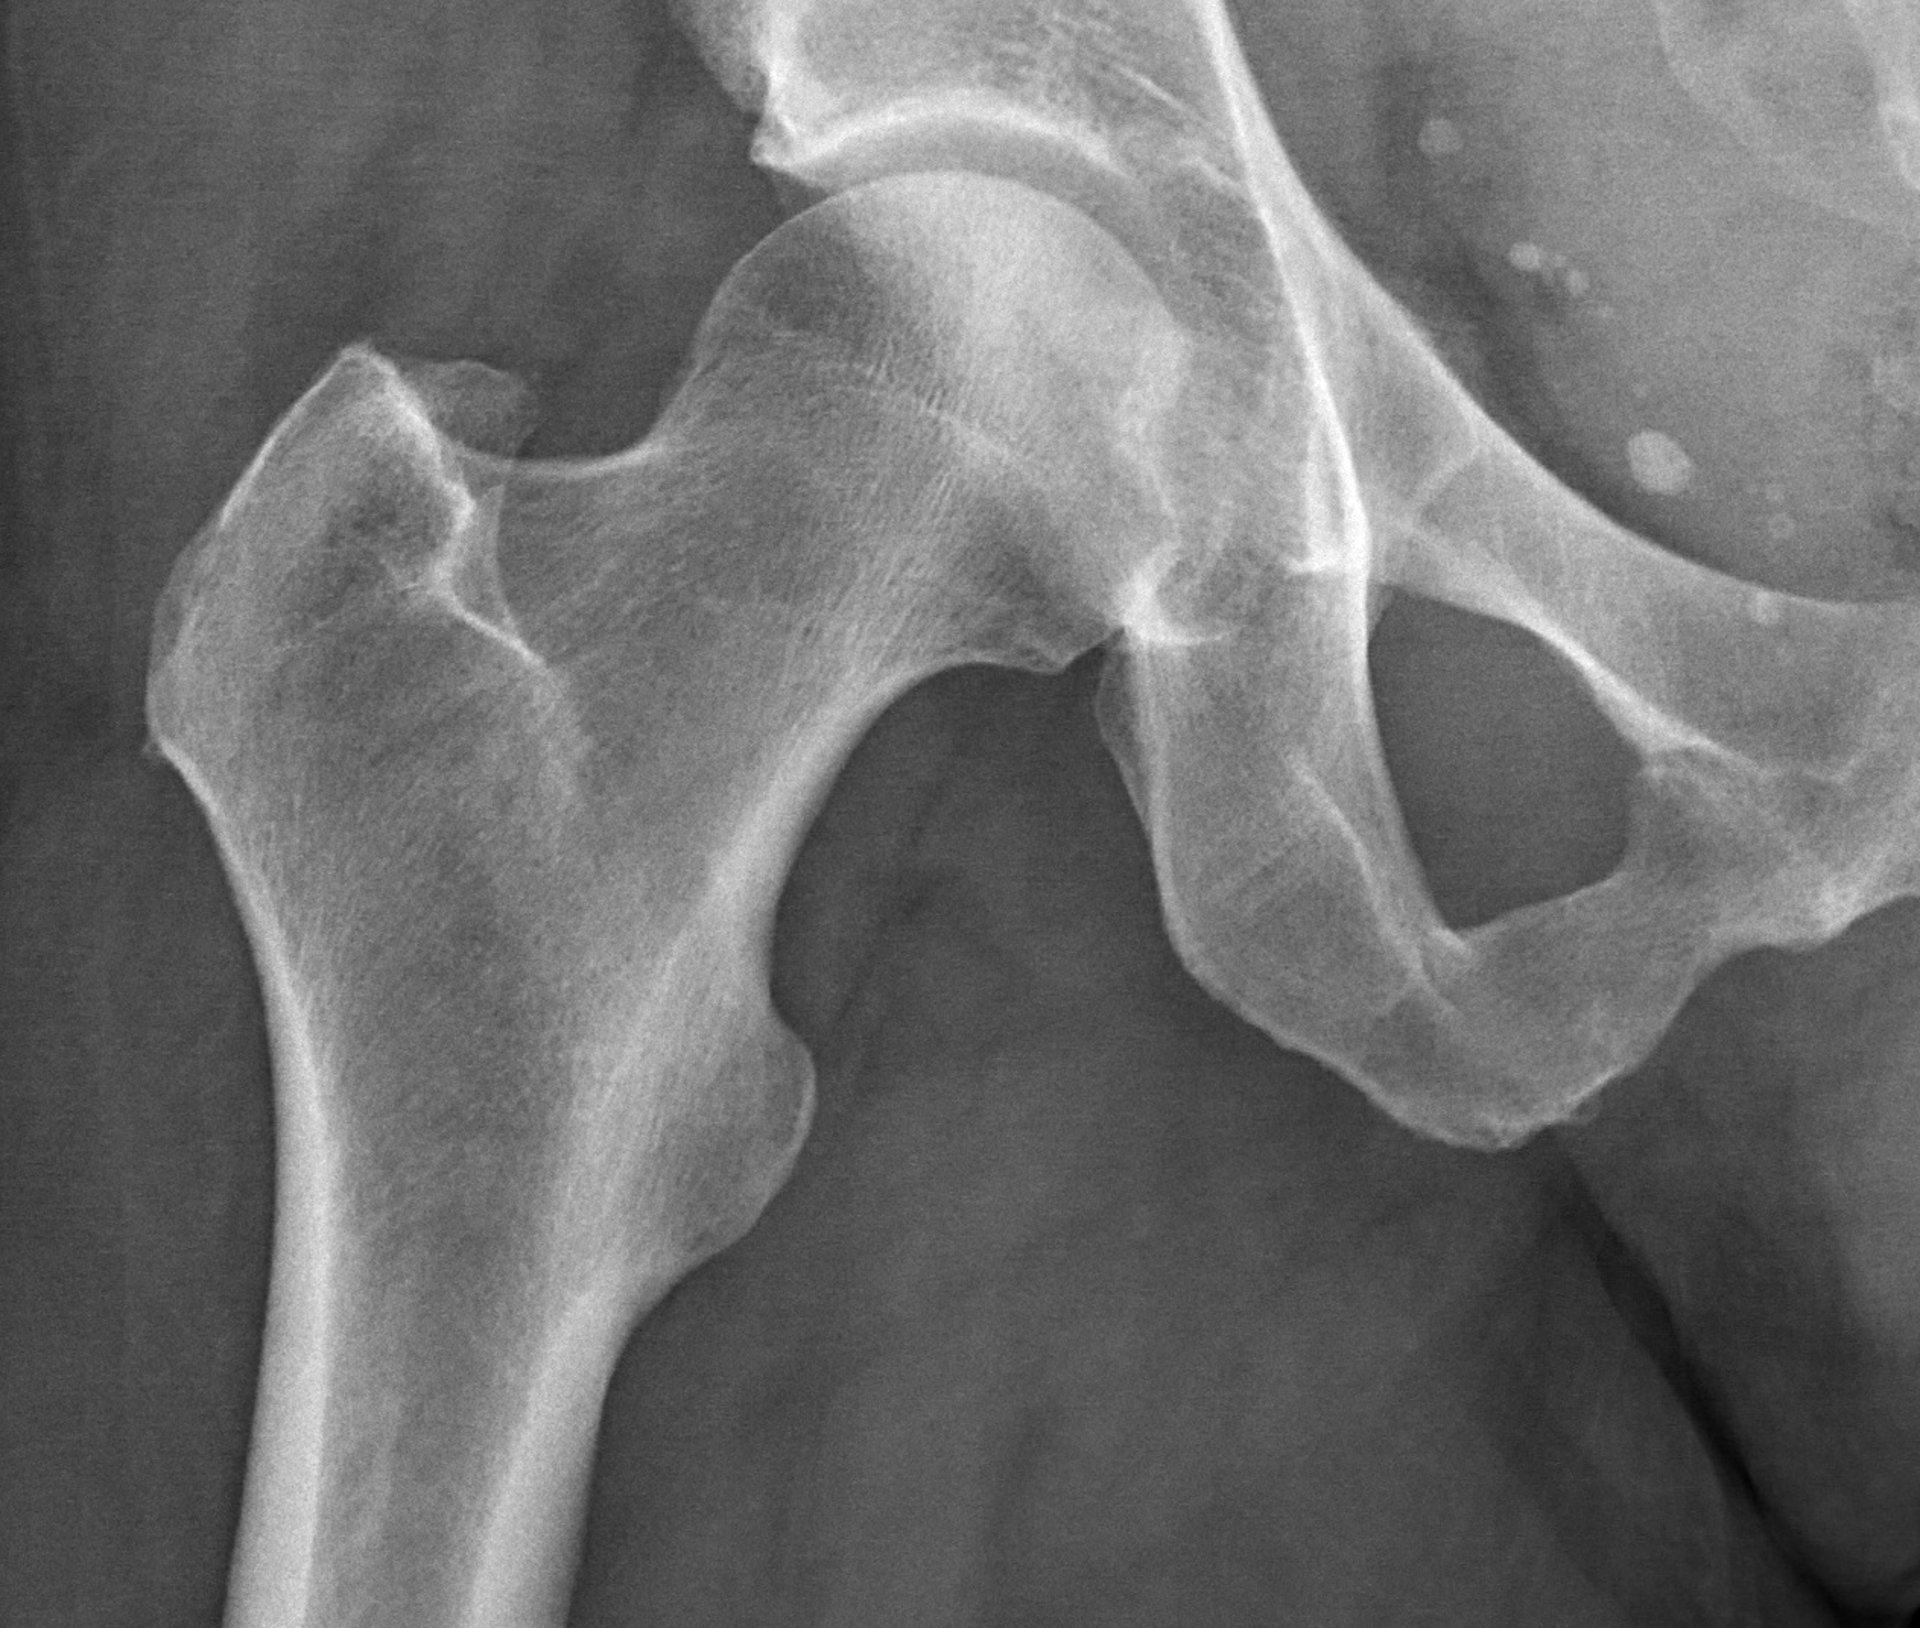

Artrosis: ¿Qué es y cómo afrontarla?

Conoce las causas de esta enfermedad, sus características y el tratamiento desde la fisioterapia.

Es fundamental entender que la presencia de artrosis no siempre equivale a dolor o limitación severa. Muchas personas conviven con los cambios articulares de la artrosis sin experimentar síntomas significativos, o con molestias leves y manejables. El impacto real en la calidad de vida se produce cuando la artrosis comienza a limitar las actividades diarias, lo que puede ir desde caminar y subir escaleras hasta tareas más sencillas.